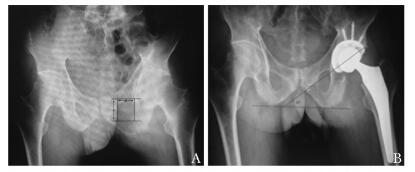

结果  患者平均随访(15.1±3.2)个月(10~21个月), 与术前相比, 末次随访时髋关节功能明显改善, 髋关节屈伸活动度由(44.3±39.6)°升高至(93.2±19.7)°; 髋关节总活动度由(64.8±54.8)°升高至(179.5±25.1)°; 髋关节Harris评分由(39.2±17.2)分升高至(87.5±4.5)分, 其中10髋优, 19髋良, 优良率96.7%(29/30);BASFI评分由(6.4±2.3)分降低至(2.2±0.9)分, 差异均有统计学意义(P均 < 0.001)。X片评估术后髋关节均未出现脱位、松动、下沉; 术后异位骨化Brooker分级:BrookerⅠ级2髋, 未见BrookerⅡ、Ⅲ、Ⅳ级异位骨化。

Results   All patients were followed up for an average of (15.1±3.2)months(ranging from 10 to 21 months); and the hip function was improved markedly after surgery. At the final follow up, the flexion-extension ROM of the hip improved from (44.3±39.6)° to (93.2±19.7)°; the total ROM improved from (64.8±54.8)° to (179.5±25.1)°; the mean value of Harris hip score improved from 39.2±17.2 to 87.5±4.5, with 10 cases rated as excellent and 19 cases as good(the rate of excellent or good result was 96.7%); the mean value of BASFI score decreased from 6.4±2.3 to 2.2±0.9. These differences were all statistically significant(P < 0.001). At the final follow up, all of the locations of the prosthesis were evaluated with X-ray, which showed no signs of aseptic loosening and dislocation of the hip prosthesis. According to Brooker grading system, only 2 hips were classified as GradeⅠ, and no hips were classified as GradeⅡ, Ⅲ, or Ⅳ.